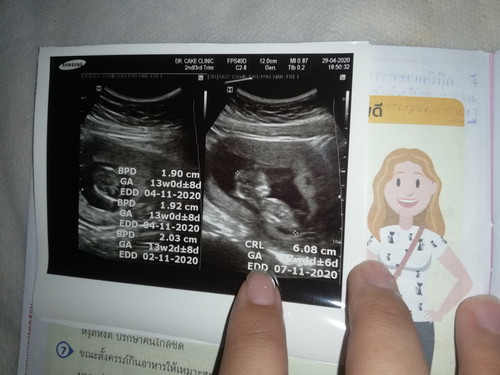

13สัปดาห์1วัน เห็นหนูไหมค่ะแม่ๆ❤️✨

ไปอัลตราซาวด์เมื่อวาน คุณหมอบอกว่าเด็กเจริญเติบโตปกติ✨ แต่เป็นห่วงที่แม่เลือดจาง และความดันสูง?✌️